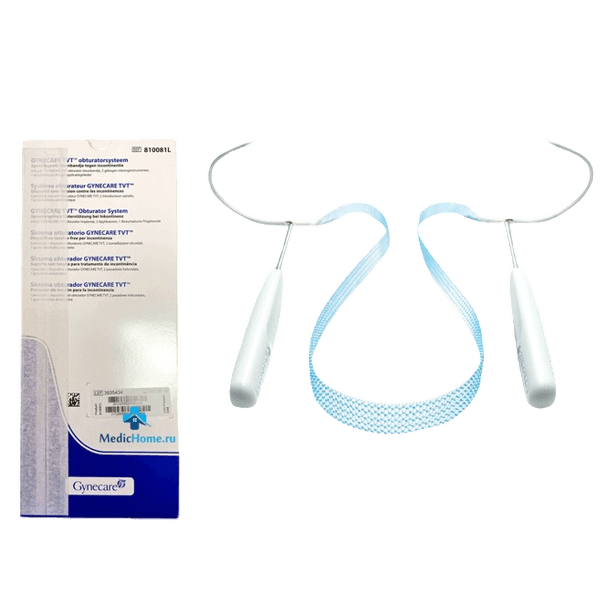

Surgical Correction for Incontinence Surgery inserting polypropylene mesh tape at mid-urethra via TVT or TOT to support the urethra. Over 90% success rate for stress urinary incontinence.